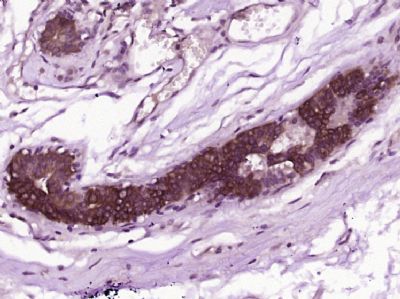

IHC (Immunohiostchemistry)

(Paraformaldehyde-fixed, paraffin embedded (Human breast cancer); Antigen retrieval by boiling in sodium citrate buffer (pH6.0) for 15min; Block endogenous peroxidase by 3% hydrogen peroxide for 20 minutes; Blocking buffer (normal goat serum) at 37 degree C for 30min; Antibody incubation with (CWH43) Polyclonal Antibody, Unconjugated (bs-9959R) at 1:400 overnight at 4 degree C, followed by operating according to SP Kit(Rabbit) (sp-0023) instructions and DAB staining.)